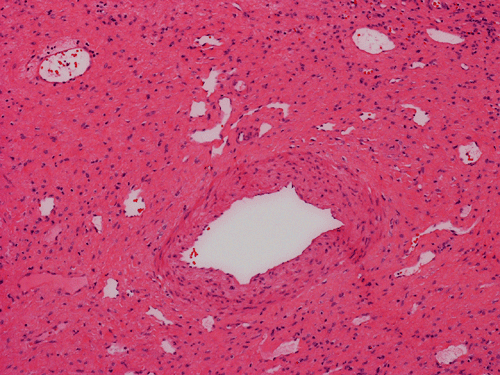

Histologically, the grossly notable nodules correspond to islands of cells separated by dense fibrous tissue  (Panel B). On medium magnification, the islands of cells have smooth, pushing margins (Panel C). The cells are quite similar to normal hepatocytes except that these islands do not have the general architecture of normal liver (Panel D). The liver plate varies from one to three cell thick is well demonstrated by reticulin stain (Panel I). In some areas there are some entrapped ductular structure consistent with bile ductules (Panel E and F) and they are well demonstrated by immunohistochemistry for cytokeratin 7 (Panel J and K). Most of these ductules are found around the fibrous scar or septa or at the edge of the nodules. Many abnormally large blood vessels are also noted and many of them are seen in the fibrous central scar (Panel G and H).

The histopathologic triad of FNH is bland hepatocytes without abnormal architecture, preserved reticulin network, the presence of bile ductules, central scar with fine fibrous septa radiating out, and the presence of large and abnormal blood vessels surrounded by a zone of connective tissue.

The central scar is composed of dense collagenous fibrous tissue with a variable number of tortuous thick-walled arteries. Fibromascular hyperplasia and myxoid degeneration are often found in these vessels.The areas away from the scaring portion and the fibrotic septa would look like normal liver at scanning magnifications. The key feature at low magnification is that no normal portal triads, no central vein or portal arteries are present. Instead, bile ductules are usually evident and often associated with chronic inflammatory cell infiltration.

Histologically, the cells in FNH are  almost identical to the normal hepatocytes surrounding hepatocytes. The reticulin network is preserved and the liver plate varies from one to three cells thick. The cells in FNA  may possess increased cytoplasmic glycogen content, focal steatosis, bile stasis, lipofuscin, iron pigment, copper deposits and Mallory bodies 4.   The central scar is composed of dense collagenous fibrous tissue with a variable number of tortuous thick-walled arteries. Fibromascular hyperplasia and myxoid degeneration are often found in these vessels.

FNH is essentially a morphologic diagnosis. Immunohistochemically, they express hepatocellular markers such as Her Par 1. They are also positive for CAM5.2, polyclonal CEA, and alpha-1- antitrypsin. CD34 is positive in endothelial cells lining the cell plates. AFP and P53 are negative. CK7 is negative in the hepatocytes but they are useful in demonstrating the proliferating bile ductules. This use, is more of educational than diagnostic purposes.

FNH and adenoma share the common features of occurring in young woman during their reproductive age and are related with the use of contraceptives. Both of them share the similar cytologic features. The cells are very similar to the normal surrounding hepatocytes. The cell plate are one to three cells thick and is best demonstrated by reticulin stain. Adenoma, however, has even stronger inclination to occur in woman. FNH and adenoma, however, have different imaging and scintigraphic characteristics. FNH reveals a homogenous enhancement with a central scar on CT and MRI and normal or increased uptake on Tc-sulfur-colloid scintigraphy. While adenoma appears as a hyperintence heterogenous mass in image and has no uptake in scintigraphy. The central scar is also helpful on histologic examination. It should be noted that the scar in small FNH may not be obvious. A high level of suspicion and careful examination is mandatory. Histologically FNH usually have ductule proliferation and hyperplastic and abnormal large vessels. The ductules are usually found in the fibrovascular areas and often at the edge of the tumor. Although large vessels are often seen in adenoma, there is no significant connective tissue zone around them. In contrast, vessels in FNH are abnormally large and are surrounded by a zone of connective tissue. Adenoma can have occasional fibrous septa which tends to be discontinuous. The fibrous scar and septa in FNH is more prominent.